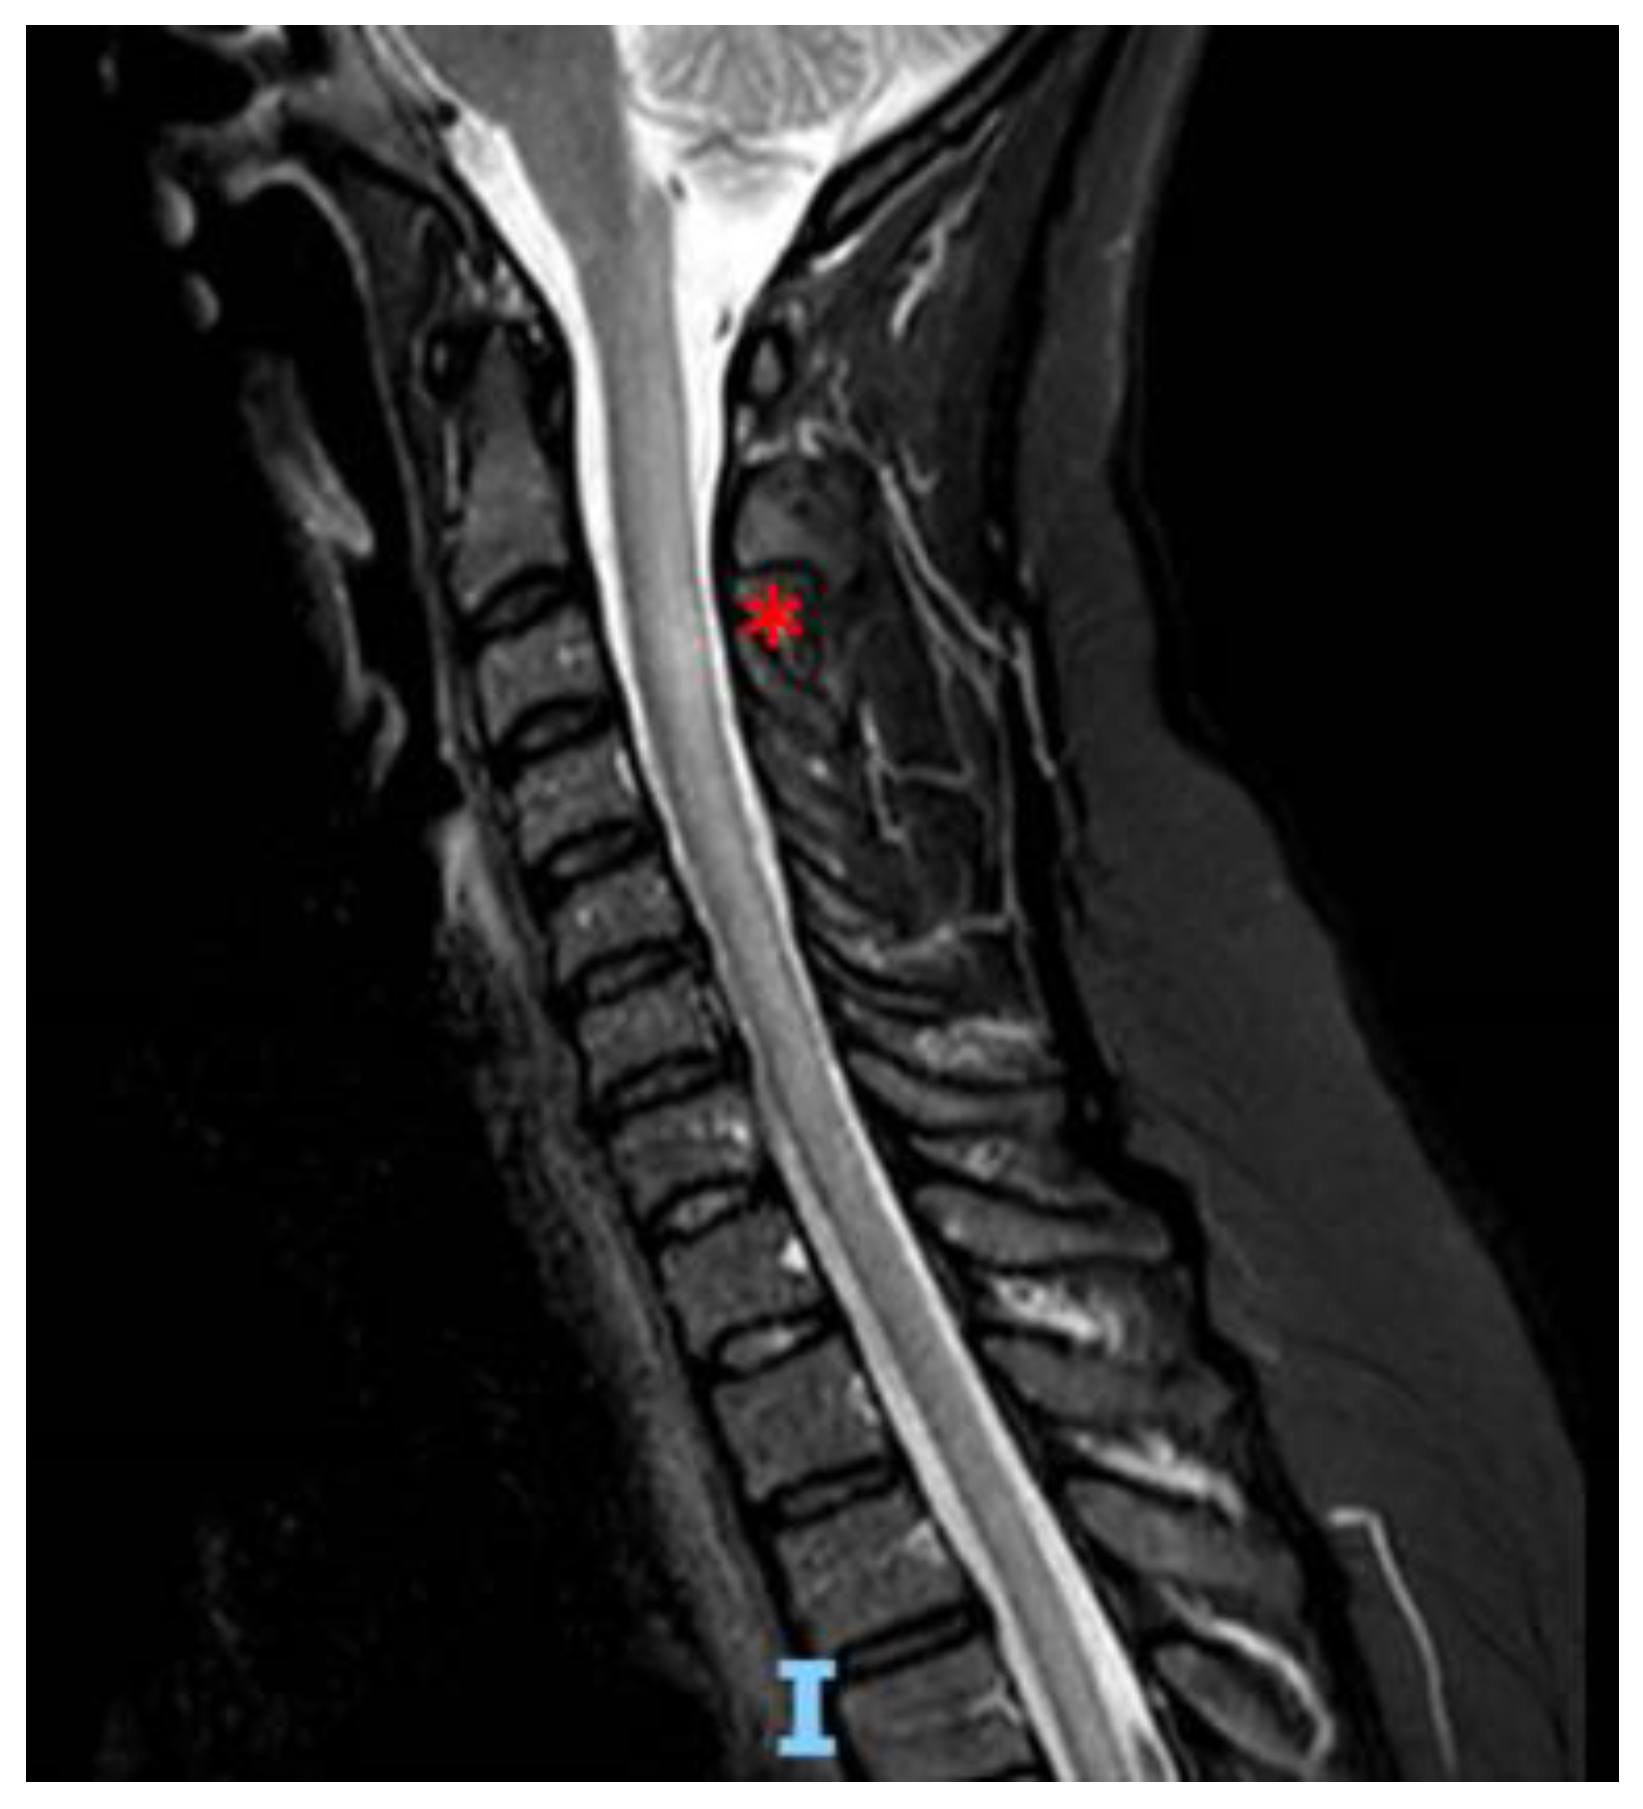

Isolated Myelopathy in Occult Breast Carcinoma with Negative Paraneoplastic Antibodies: A Case Report of a Rare Condition

2. Case Report